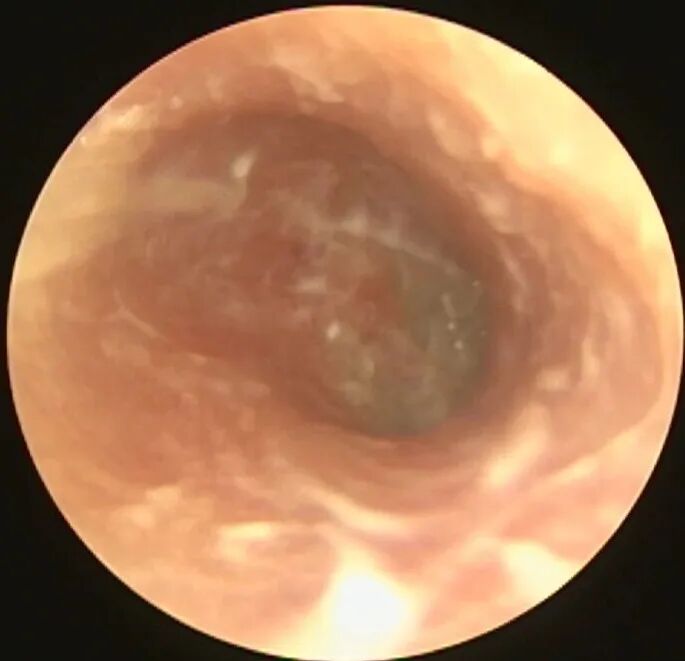

但是有时虽然看不到菌毛和孢子,但实际上也是真菌感染,比如: